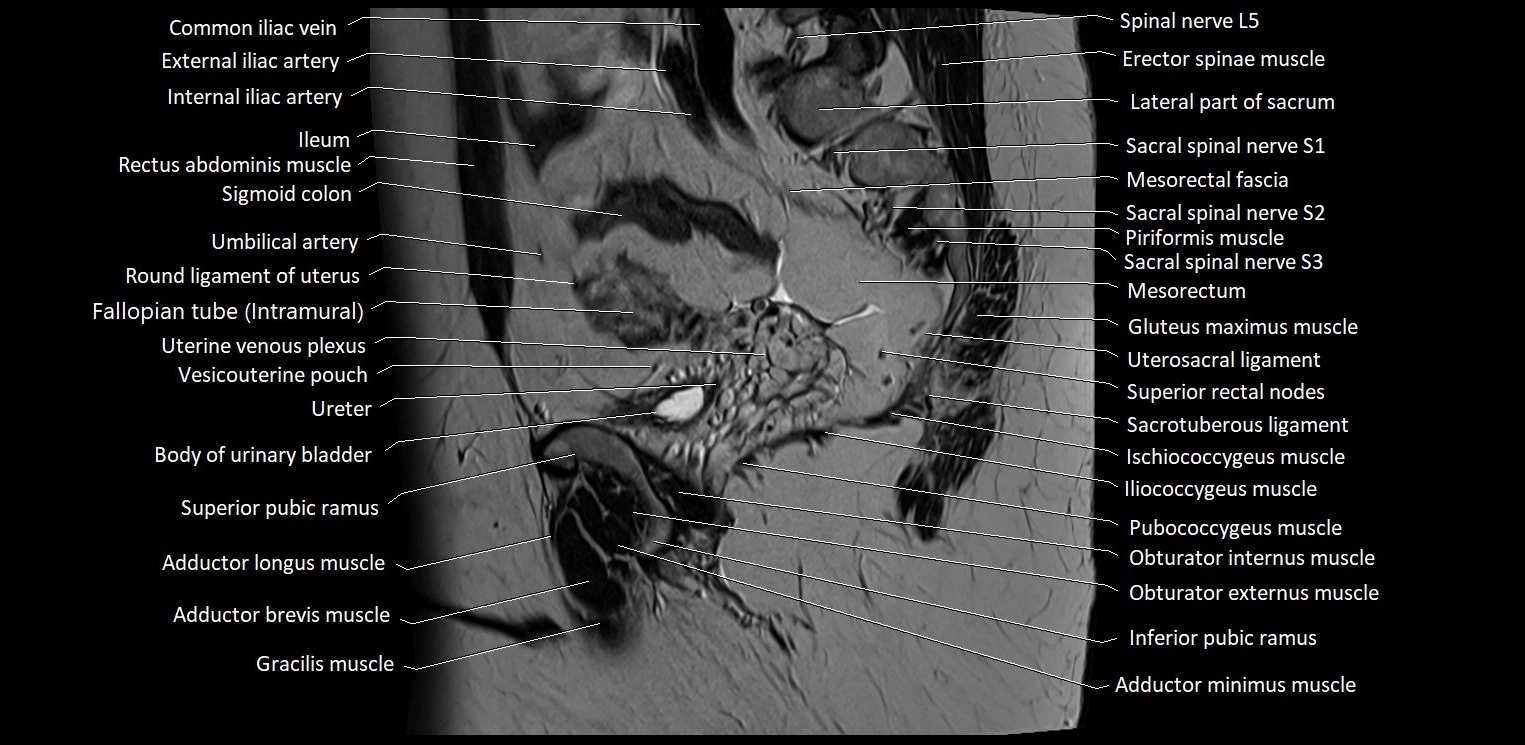

- Adductor brevis muscle

- Adductor longus muscle

- Adductor minimus muscle

- Body of urinary bladder

- Common iliac vein

- External iliac artery

- Gracilis muscle

- Ileum

- Iliococcygeus muscle

- Inferior pubic ramus

- Internal iliac artery

- Mesorectal fascia

- Mesorectum

- Obturator externus muscle

- Obturator internus muscle

- Pubococcygeus muscle

- Round ligament of uterus

- Sacrotuberous ligament

- Spinal nerve L5

- Spinal nerve S1

- Spinal nerve S2

- Spinal nerve S3

- Superior pubic ramus

- Umbilical artery

- Uterosacral ligament

- Vesicouterine pouch